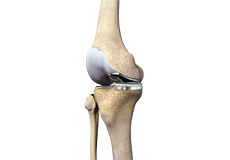

ACL Preserving Total Knee Replacement

ACL preserving total knee replacement is an advanced surgery performed to replace a damaged knee joint with a prosthesis while preserving the anterior cruciate ligament (ACL). The ACL is a very important ligament that runs diagonally across the front of the knee and provides rotational knee stability.